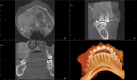

A 30-year-old woman presented for orthodontic treatment, with a chief symptom of a 'shifting bite' and concurrent facial asymmetry with aesthetic concerns. The patient had previously received treatment from several general dentists and several specialists, without accurate diagnosis. Radiological investigation coupled with biopsy confirmed a diagnosis of fibrous dysplasia. Proper diagnosis led to changes in the treatment plan and gave the patient realistic expectations about the options she had for the outcome of treatment. Prompt diagnosis by dental practitioners is critical to patient satisfaction and successful outcome; therefore, it is important to familiarise ourselves with the signs, symptoms and proper course of management of fibrous dysplasia.